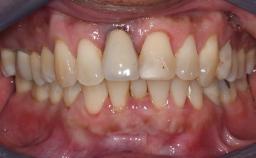

Management of a Fractured Implant Supporting a Screw-retained Metal-ceramic Restoration

The fracture of an implant after it has been restored is one of the most severe complications. It most frequently occurs in partially edentulous jaws (1.5%). Most implant fractures involve implants with a diameter of 3.75 mm made of commercially pure titanium (Eckert 2010). Unfortunately, many cases are not reported or documented by the clinicians involved in resolving the problems created by the fracture. This case report describes the management of an implant fracture at site 36 in a middle-aged male patient. The implant had been restored with a screw-retained metal-ceramic crown.